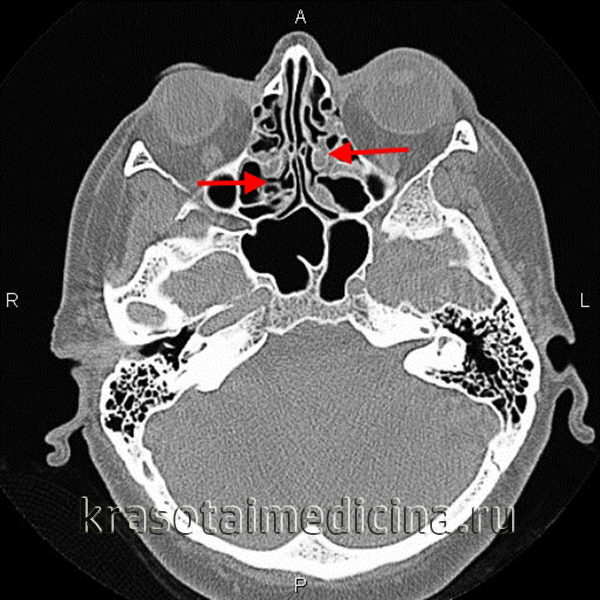

- Рентген пазух.Рентгенография придаточных пазух - базовый метод диагностики при этмоидите. Рентгенологически поражение ячеек лабиринта проявляется затемнением их просвета, снижением пневматизации, неровностью и утолщением или дефектами костных стенок. При эмпиеме возможна визуализация уровня жидкости.

- Томография.Компьютерная томография синусов используется при низкой информативности рентгенографии, признаках орбитальных или внутричерепных осложнений. Кроме того, исследование применяется для достоверной дифференциальной диагностики с другими патологиями. При необходимости сочетается с МРТ придаточных пазух носа.